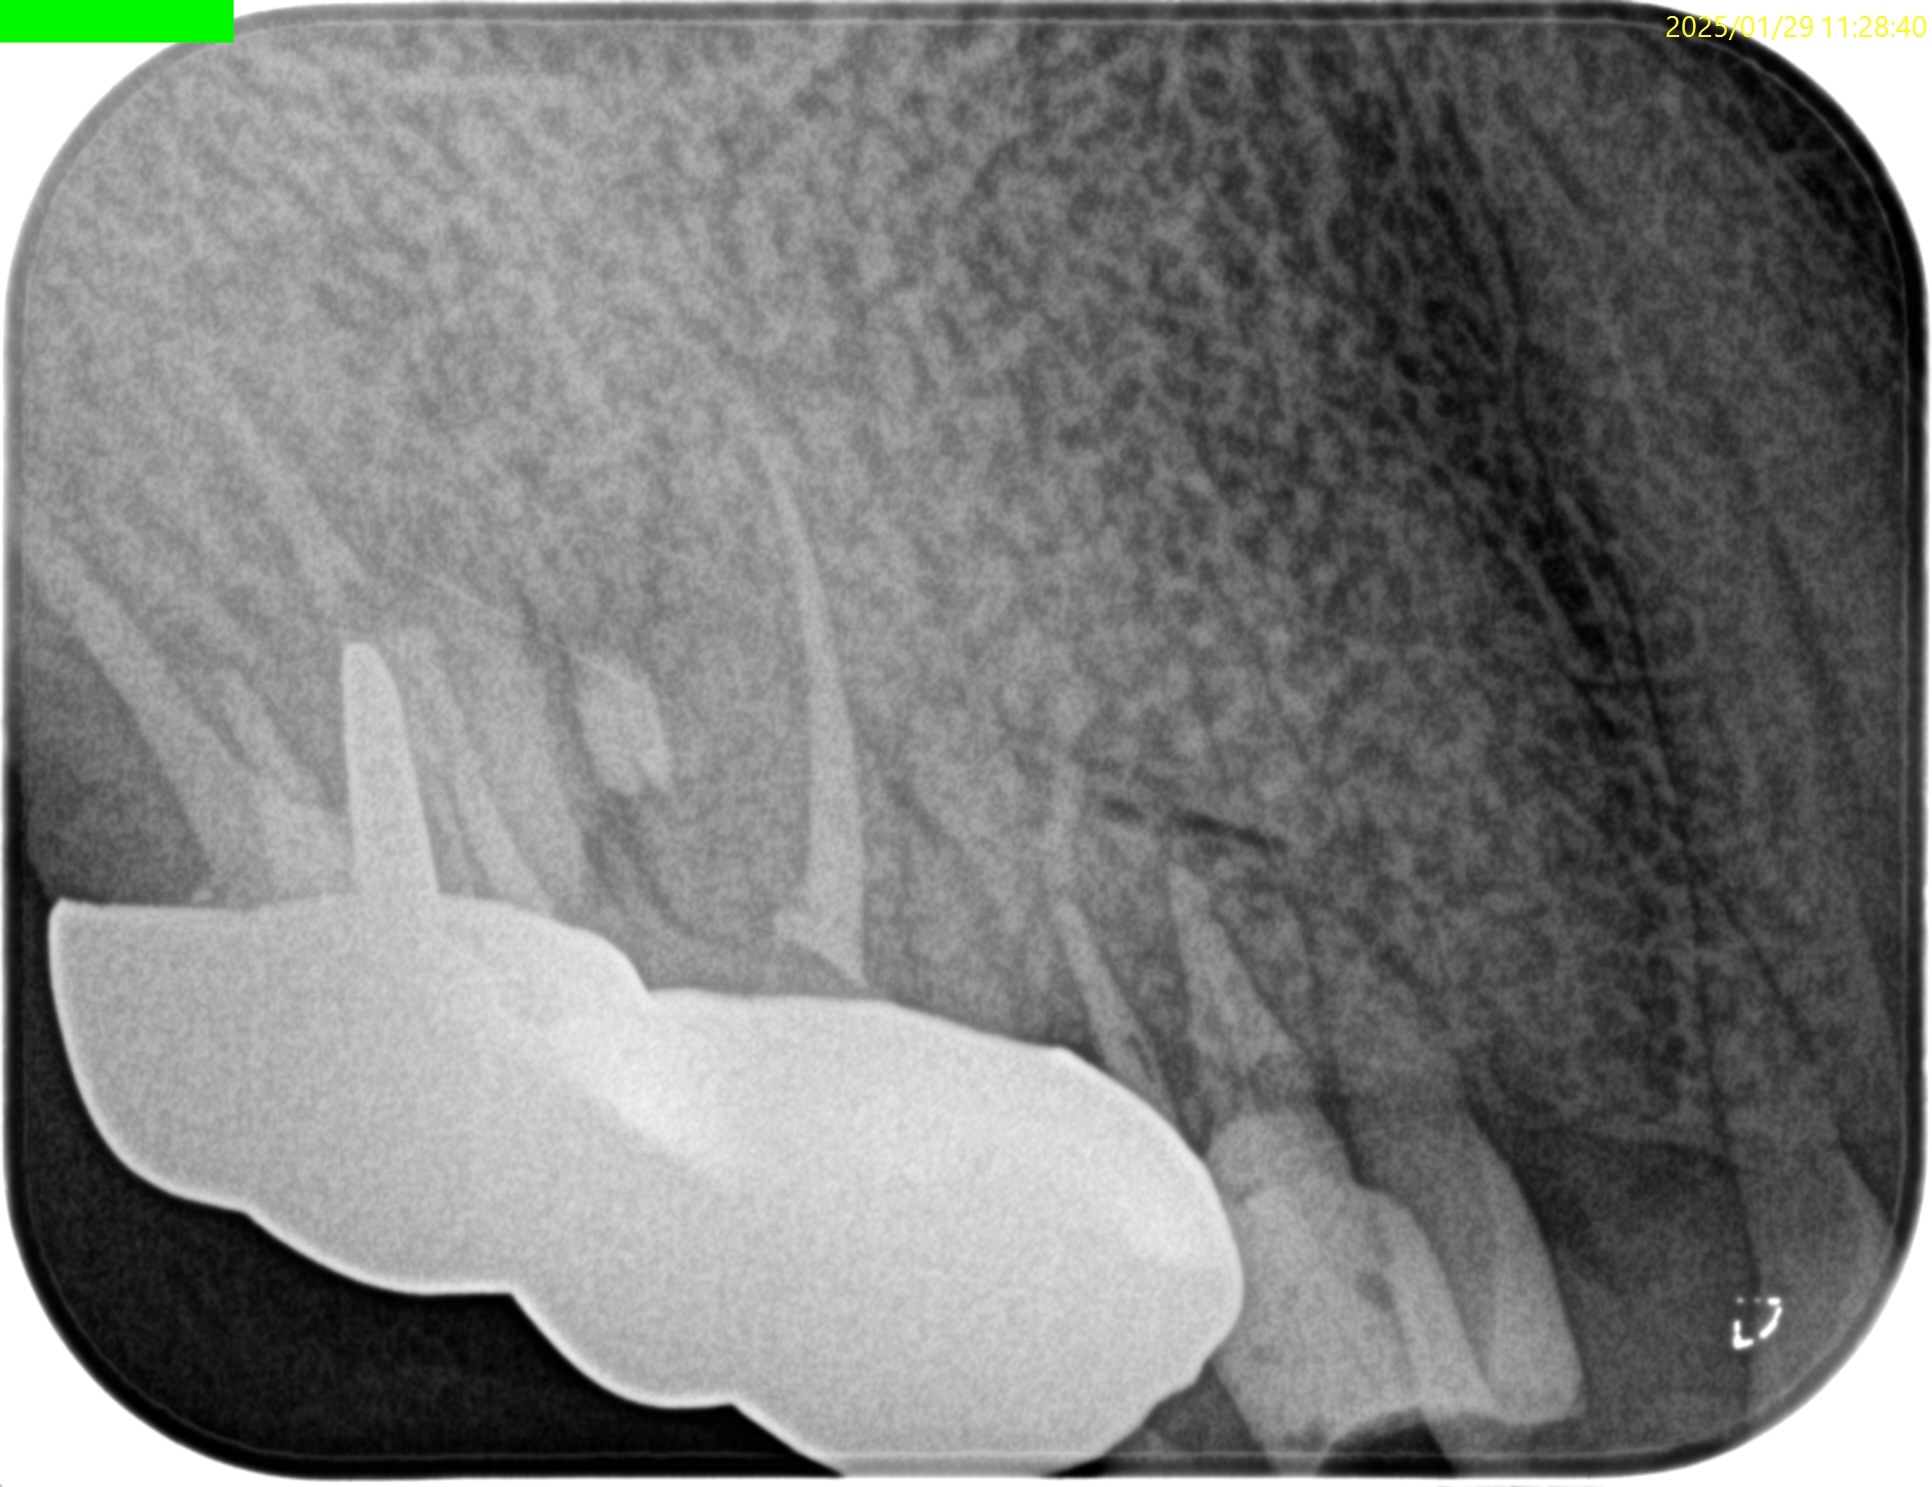

PA(2024.10.28)

CBCT(2024.10.28)

#4

歯根の中央で水平に破断している。

ここで重要なことは破折片の口蓋側寄りの歯根には病変がないということだ。